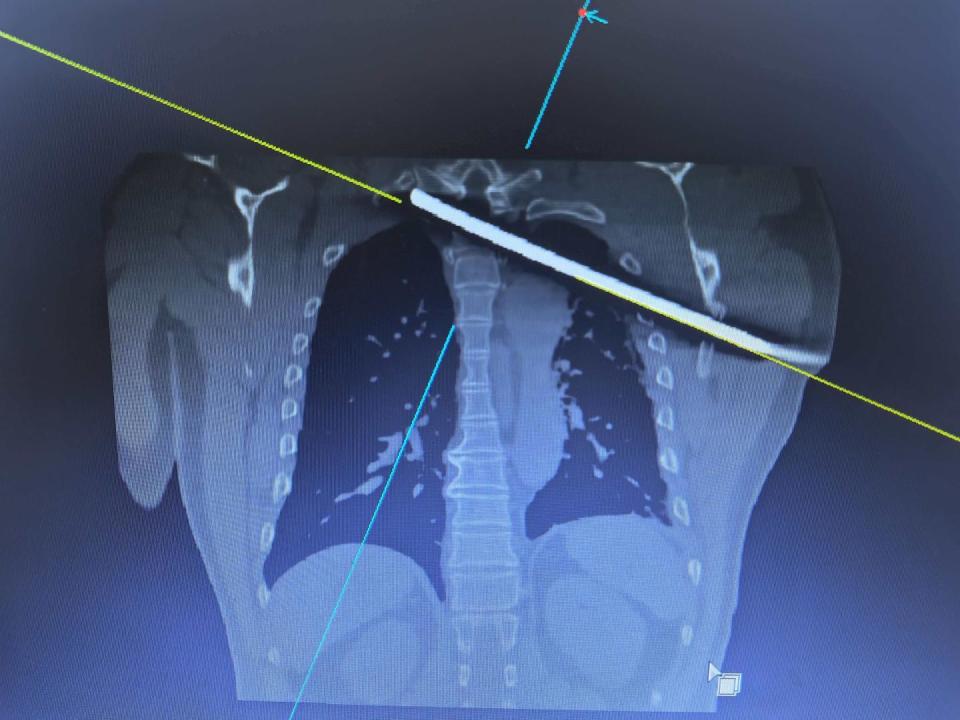

▲斜插进体内的钢筋

刘先生的伤到底有多严重?医院骨科副主任医师张坤告诉记者,患者术前影像与床旁评估显示,钢筋紧贴主动脉弓、穿过椎管、贴近脊髓,没入体内的长度达30厘米,“手术过程中稍有不慎,就可能对伤者带来二次伤害,因此我们将‘防大出血、防二次神经损伤’设为首要目标,联合胸外科、麻醉科等多个部门共同手术,从当天晚上11点多一直持续到第二天早上6点,才将钢筋顺利取出。”

▲插进体内的钢筋长约30厘米